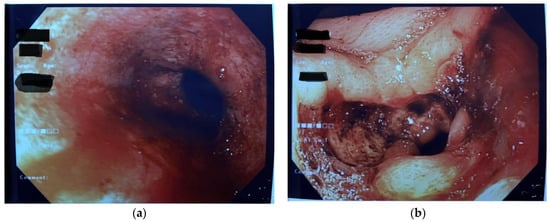

- Plessi, C.; Sica, M.; Molinaro, F.; Fusi, G.; Rossi, F.; Costantini, M.; Roviello, F.; Marano, L.; D’ignazio, A.; Spinelli, C.; et al. Diagnosis and treatment of primary hypertrophic pyloric stenosis (HPS) in older children. J. Pediatr. Surg. Case Rep. 2021, 69, 101860. [Google Scholar] [CrossRef]